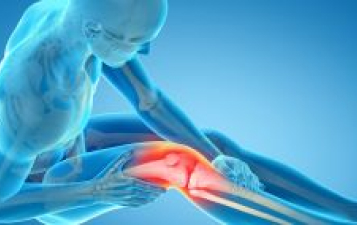

Knee joint replacement surgery, also known as knee arthroplasty, is a highly effective procedure for individuals suffering from severe arthritis, knee injuries, or long-term wear and tear. The surgery involves replacing damaged or diseased parts of the knee joint with artificial components to relieve pain and restore function.